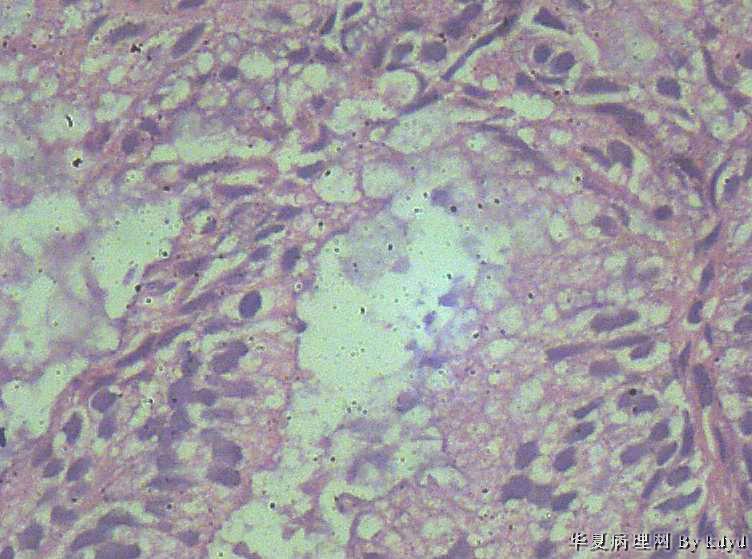

51岁,停经一年后,阴道流血。行宫腔诊刮。

B超示:宫腔有一赘生物大小1.5*2.5大小。

肉眼观:少许粘液及碎组织。(全包)

疑问:1。腺体呈复杂性增生伴不典型增生?

2。腺体有分泌反应,有些腺体看上去又像是宫颈的腺体(手术医生说是宫腔取的)?

3。怎样报告???

• 腺体非典型增生?是宫腔还是宫颈??图1

• 腺体非典型增生?是宫腔还是宫颈??图2

图2

• 腺体非典型增生?是宫腔还是宫颈??图3

图3

• 腺体非典型增生?是宫腔还是宫颈??图4

图4

腺体密集,有背靠背、共壁,有乳头状结构,有核异性性,有病理核分裂:

子宫内膜中-重度不典型增生,癌变不能排除

宫内膜样癌(高分化)。组织腺体拥挤、背靠背、血管纤维轴心乳头状,间质细胞消失代之纤维。